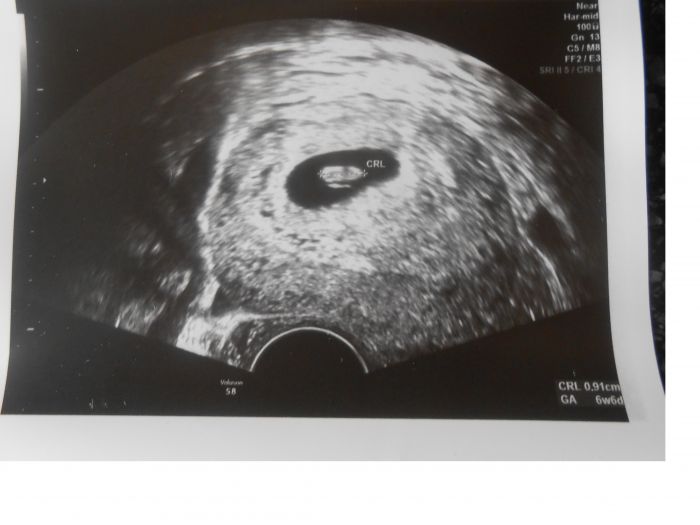

Mě fotečku z UZ poslal na e-mail, na první toho taky moc vidět není. Je to 8tt. Tak taky doufam,že na další kontrole 24.9. bude už něco k vidění. A já taky nic neplatím, ani minulé těhu jsem nic neplatila. Jen mi to poslal i s tou cystou, co mám vlevo na vaječníku.